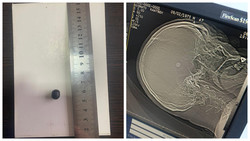

Жалал-Абадда шок абалда ооруканага түшкөн адамдын башынан ок алып чыгышты. Учурда абалы кандай?